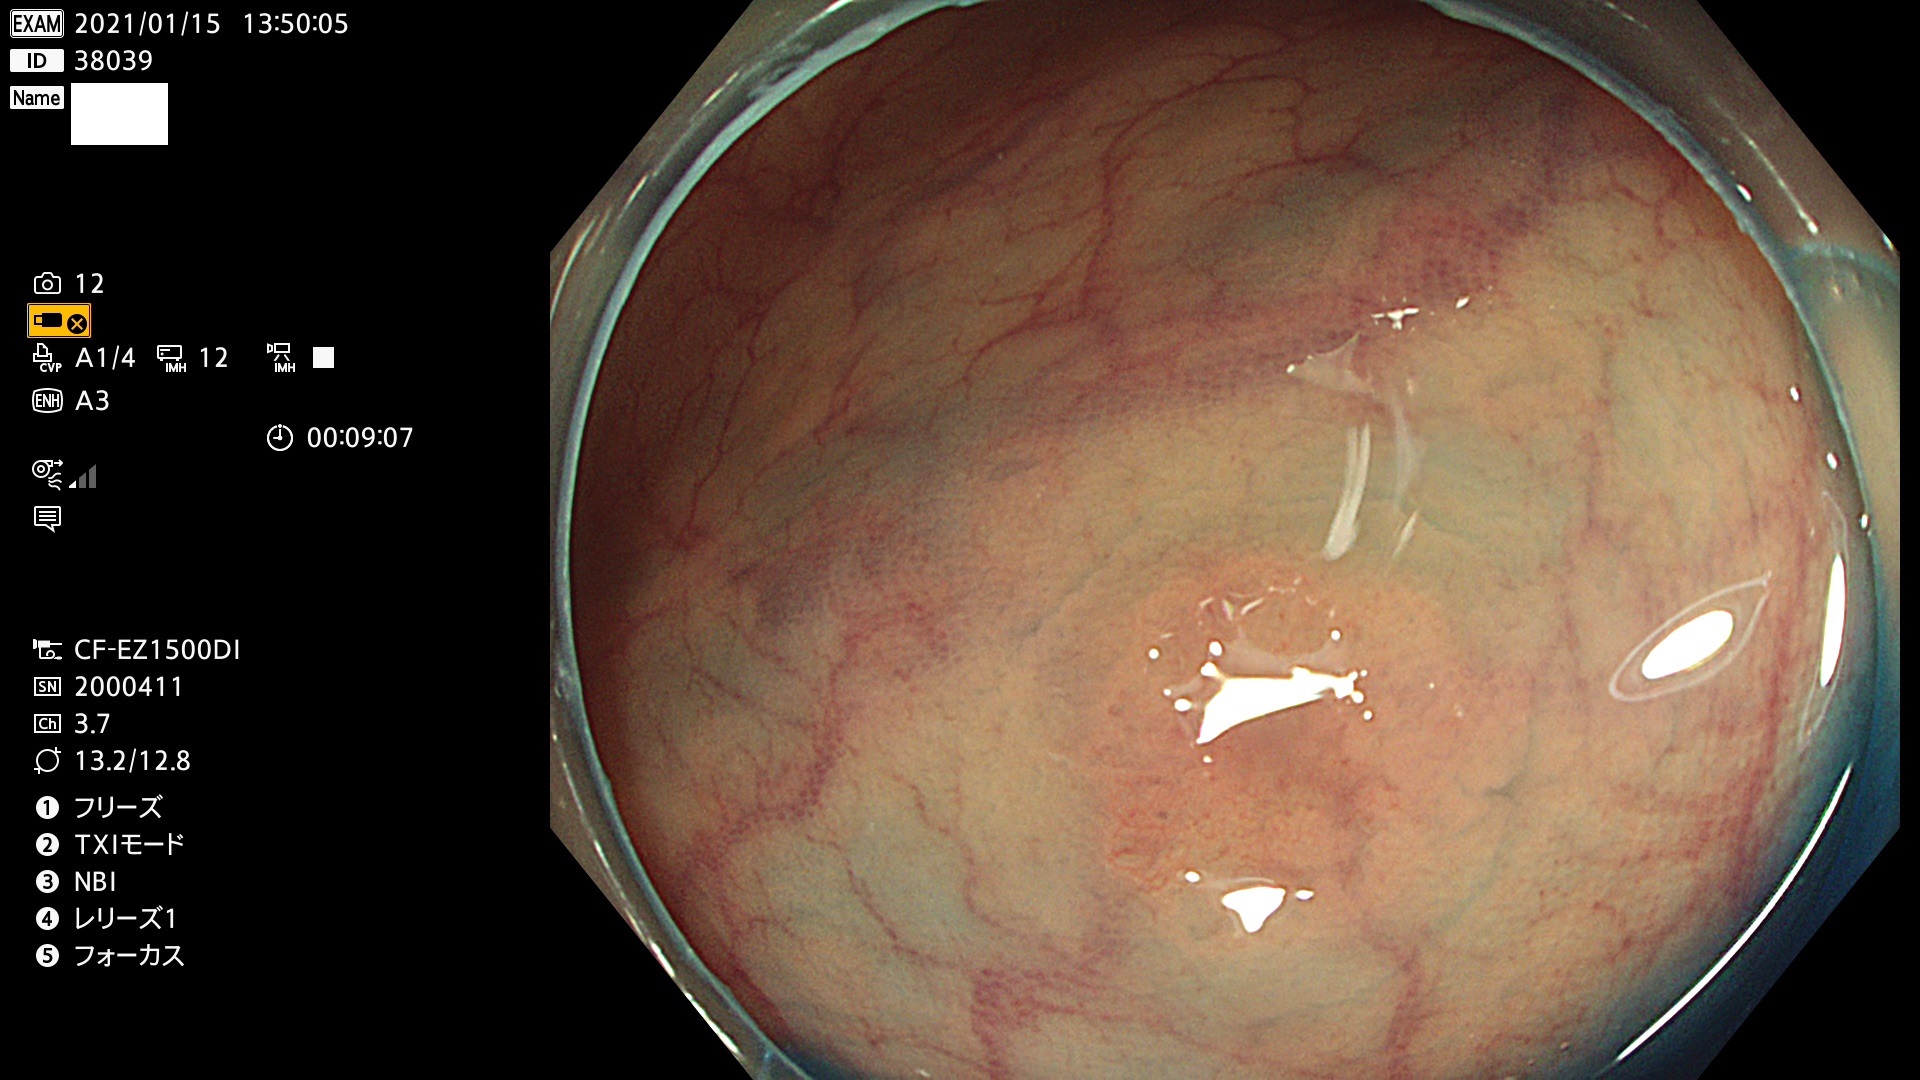

38001 38002 38003 38004 38006(SSAPのみ) 38007 38008 38009 38010 38012 38013 38014 38016 38018 38020 38021 38025 38026 38029 38032 38033 38034 38035 38036 38037(SSAPのみ) 38039 38043 38044 38048 38049 38050 38052 38055 38056 38057 38058 38059 38064(SSAPのみ) 38065 38068 38069 38070 38071 38072 38074 38075 38076 38078 38079 38080 38082 38083 38084 38085(SSAPのみ) 38086 38087 38088 38089 38090 38091 38092 38093 38094 38097 38098 38099

発見困難で危険性の高い平坦型病変(上記100名より抽出)